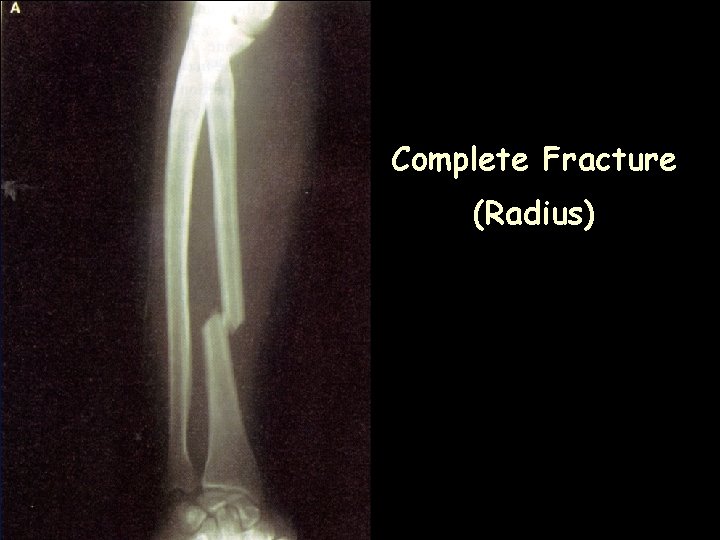

Complete Fracture (Radius)